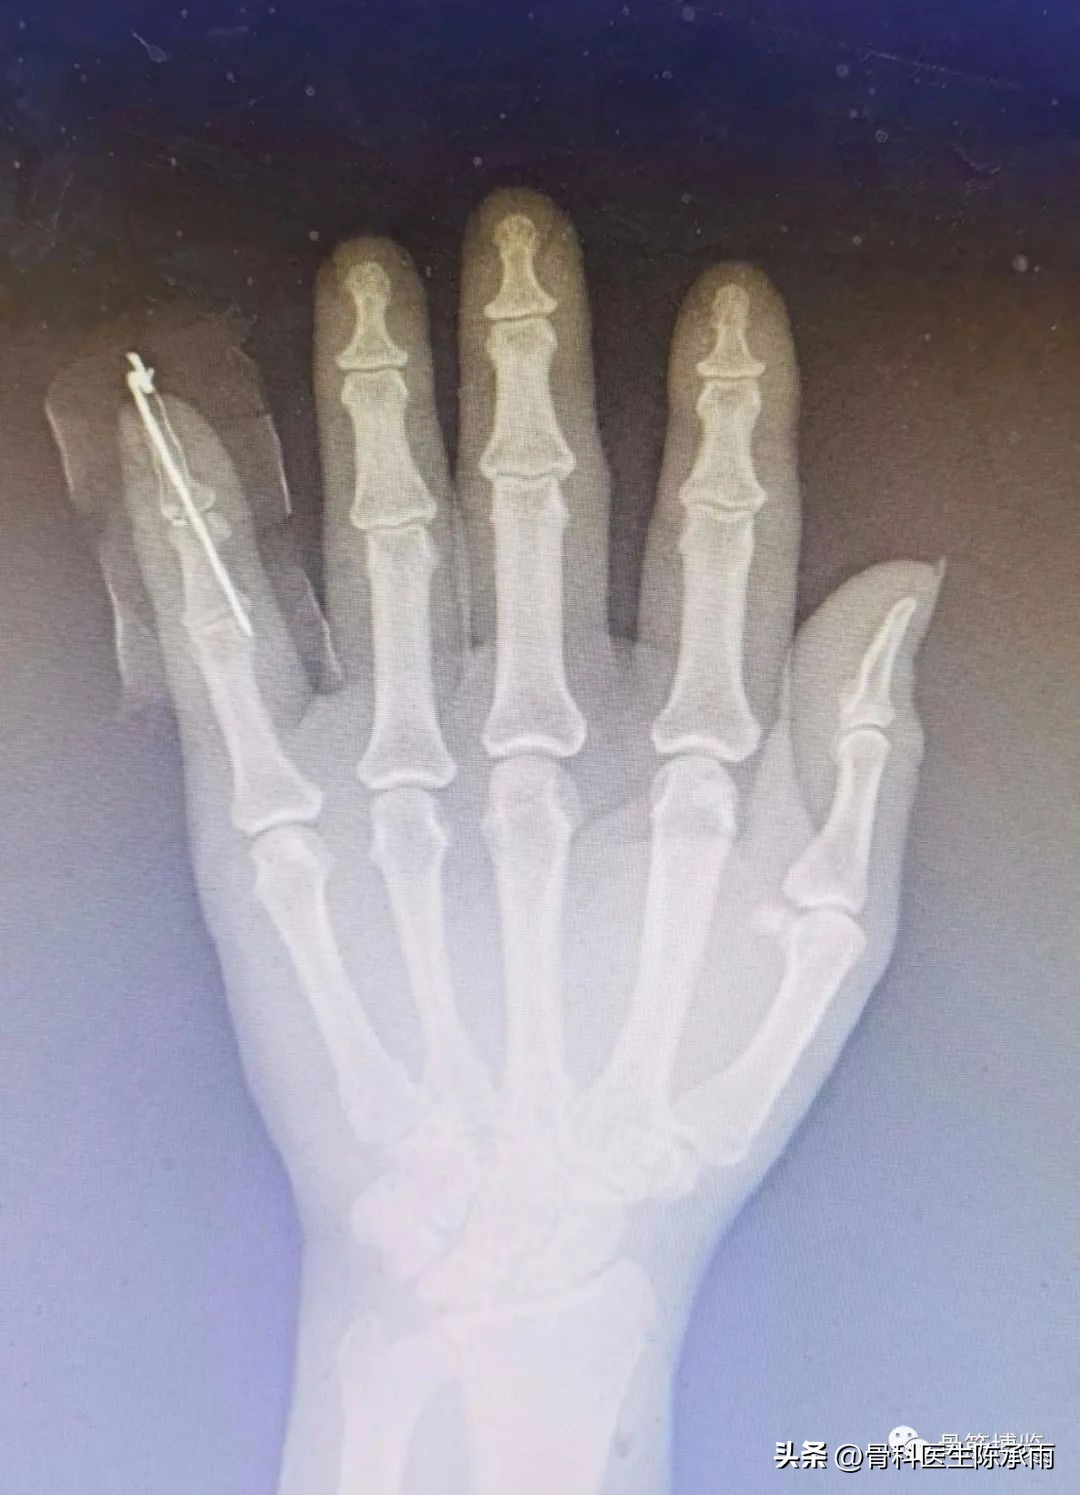

手指像个锤子!

手指发生损伤后,手指最末一节不能主动伸直,被动可以伸直,手指像锤子头一样弯下来。弯曲不受影响。最末的关节背侧可以有些肿胀。

锤状指是手指伸肌腱止点处撕脱或同时伴有远节指骨背侧关节缘骨折。一般是伸直位急性屈曲力量挫伤所致,常见于小指、环指和中指,如未予治疗可能发展为鹅颈畸形和伸指装置松弛。

1、Wehbe´ and Schneider 根据侧位X线片表现分型

- I:远侧指间关节无半脱位

- II:有半脱位

- III:有干骺端和骨干的损伤

2、根据骨折块大小分:

- a:小于1/3关节面

- b:1/3-2/3关节面

- c:大于2/3关节面